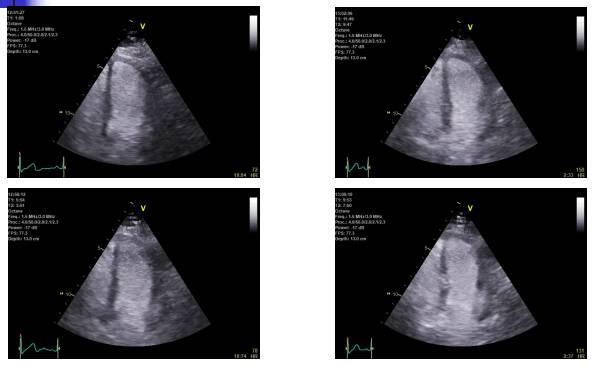

超声心动图

◆主要用于检测存活心肌的收缩功能储备

◆小剂量多巴酚丁胺负荷超声心动图(DSE)已成为识别存活心肌(冬眠心肌)的重要方法。

◆静脉注射低剂量多巴酚丁胺(5~10μg·kg-1·min-1)后功能障碍心肌收缩能力增强,提示存在收缩功能储备(反映心肌存活)。

◆而应用高剂量多巴酚丁胺(20~40μg·kg-1·min-1)后出现新的室壁运动异常,提示存在可诱导的心肌缺血。

◆心肌声学造影(Myocardial Contrast Echocardiography, MCE)也被推荐用于评价存活心肌和可逆心肌缺血。

前壁心肌梗死后,多巴胺负荷试验,分别是基础状态、负荷高峰、恢复期5分钟、10分钟